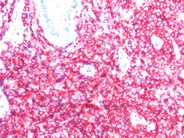

Leukemia Cutis - 1.

Leukemia Cutis - 1. from imagebank.hematology.org

Immunophenotypic identification of acute myeloid leukemia with monocytic differentiation. While the extramedullary collection of leukemic cells is generally regarded as myeloid sarcoma. The role of splenic irradiation in chronic lymphocytic leukemia, cancer (philad.), v. Leukaemia cutis refers to the infiltration of the skin with leukaemia cells. Leukemia usually involves the white blood cells. Leukemia cutis—epidemiology, clinical presentation, and differential diagnoses. Leukaemia cutis is an uncommon condition due to infiltration of. Leukaemia is the name given to a group of blood disorders in which there is a malignant proliferation of white cells (leukocytes).

Immunophenotypic identification of acute myeloid leukemia with monocytic differentiation. Leukemia cutis is the infiltration of neoplastic leukocytes or their precursors into the epidermis, the dermis, or the subcutis, resulting in clinically identifiable cutaneous lesions. Lc and aml leukemia cutis most commonly is observed in aml compared to the other types of leukemia. Leukemia cutis is the infiltration of neoplastic leukocytes or their precursors into the epidermis, the dermis, or the subcutis, resulting in clinically identifiable cutaneous lesions. Leukemia is a cancer of the blood and bone marrow.